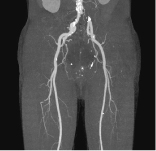

下肢動脈VR -

下肢動脈MIP -

下肢動脈拡大VR